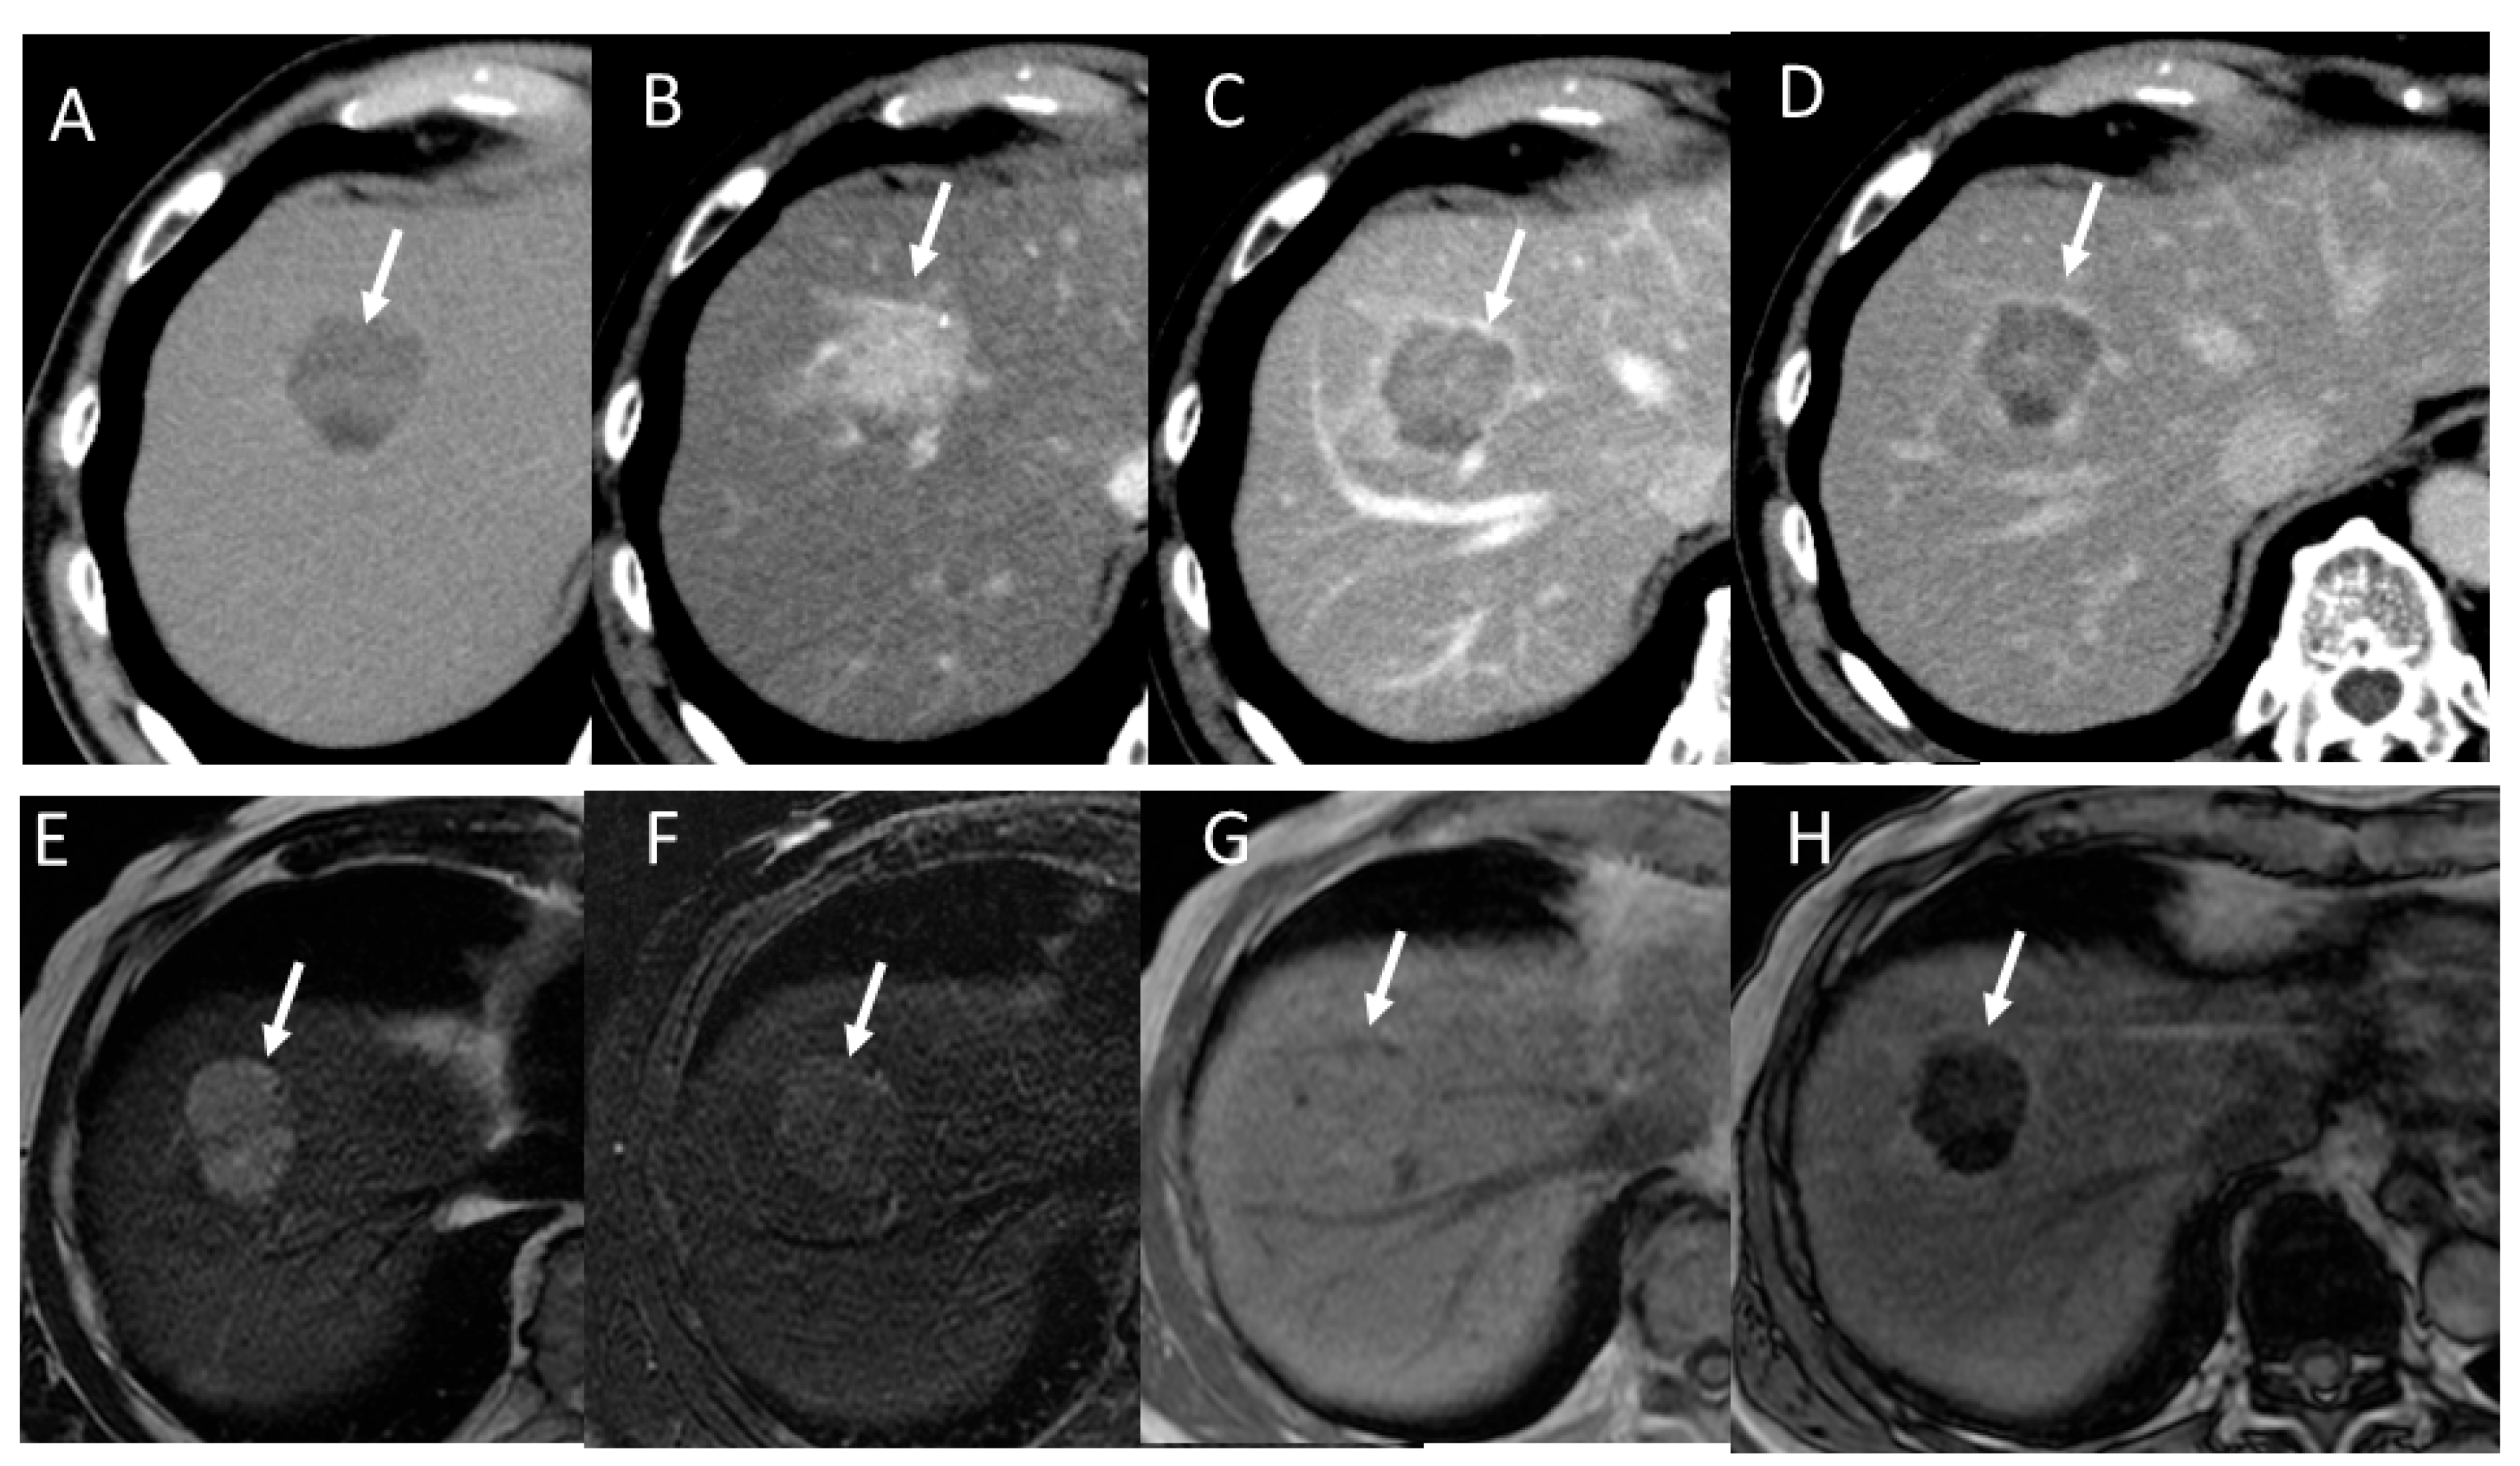

2.1. HCC Imaging on CT

2.2. HCC Imaging on MRI

4.6. Fibrolamellar Hepatocellular Carcinoma (FL-HCC)

4.7. Combined Hepatocellular and Cholangiocarcinoma (cHCC-CCA)

4.8. Steatohepatitic HCC (SH-HCC)